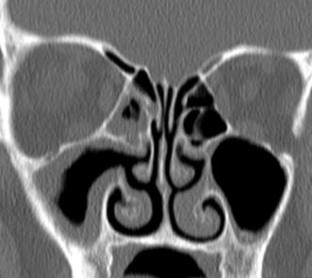

Fig. 1